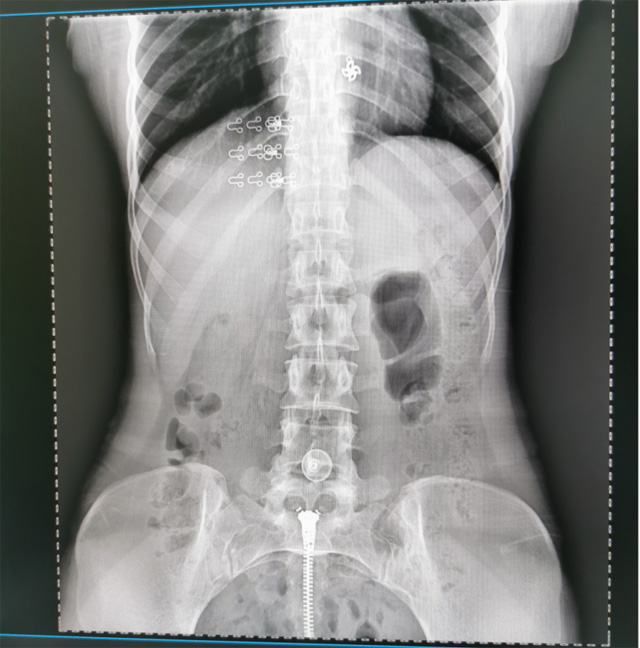

提高醫(yī)院的影像科的醫(yī)療服務(wù)水平,滿足滿足人民群眾不斷增長(zhǎng)的醫(yī)療需求,促進(jìn)醫(yī)療技術(shù)快速發(fā)展。醫(yī)院都引進(jìn)懸吊DR拍片設(shè)備新一代數(shù)字化X線攝影系統(tǒng)。標(biāo)志著醫(yī)院的診療水平又上升一個(gè)新的臺(tái)階。懸吊DR滿足人體頭部、胸部、腹部、腰椎、四肢等部位的數(shù)字?jǐn)z影檢查,可以檢查呼吸系統(tǒng)疾病,心臟系統(tǒng)的疾病、骨關(guān)節(jié)系統(tǒng)的疾病,子宮輸卵管造影、胃腸道造影,.有職業(yè)病體檢篩查塵肺病功能。通過(guò)DR數(shù)字化攝影,分段連續(xù)、重疊采集數(shù)字化圖像,利用軟件對(duì)圖像進(jìn)行拼接的方式來(lái)獲得全脊柱、全上肢或全下肢的圖像。新設(shè)備的圖像更清晰,臨床拍攝避免患者再次搬運(yùn)和移動(dòng)產(chǎn)生的痛苦,是創(chuàng)傷骨折患者的福音。輻射減少受照劑量50%,后處理能力強(qiáng)、圖像質(zhì)量高。有效降低操作難度,縮短工作流程,尤其適合大批量體檢。